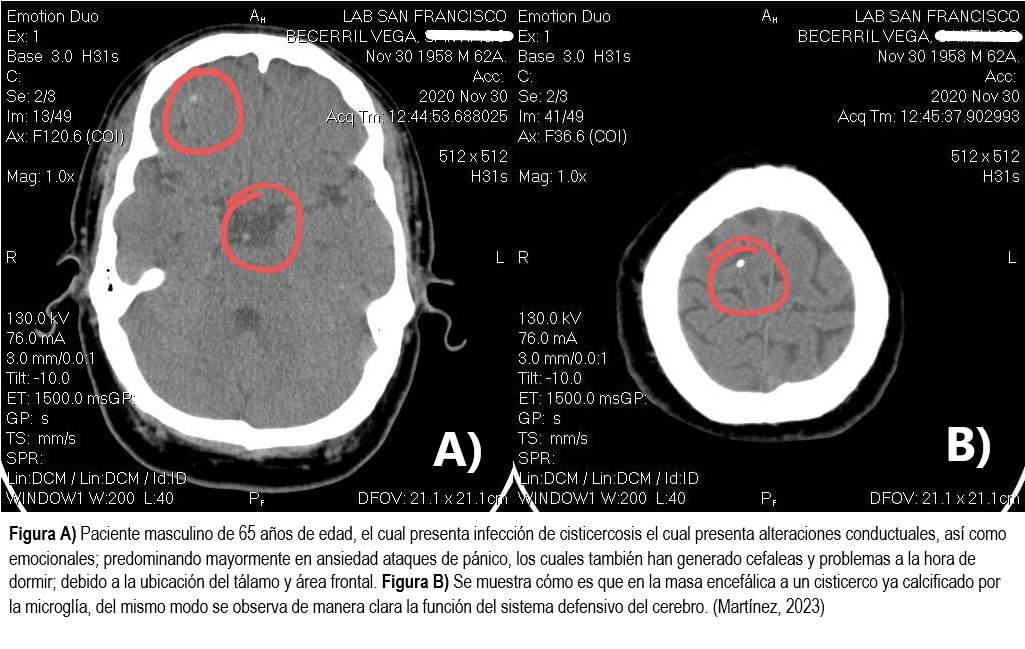

Cambios en la personalidad y el comportamiento: También pueden provocar daño cerebral debido a la inflamación y la presión que ejercen sobre los tejidos cerebrales, particularmente en áreas talámicas, orbitofrontales y áreas geniculaterales (Ver imagen 1). Esto puede afectar diferentes áreas del cerebro, incluidas aquellas que regulan la conducta, emociones y toma de decisiones (Martínez, 2016).

- Martínez, G. (2023). Daños neurobiológicos y neuropsiquiatricos de trastornos mentales causado por daños adquiridos. En Instituto de Seguridad y Servicios Sociales de los Trabajadores del Estado [ISSSTE]. Congreso Internacional de Neurología y Neurocirugía, Ciudad de México, Centro, México.